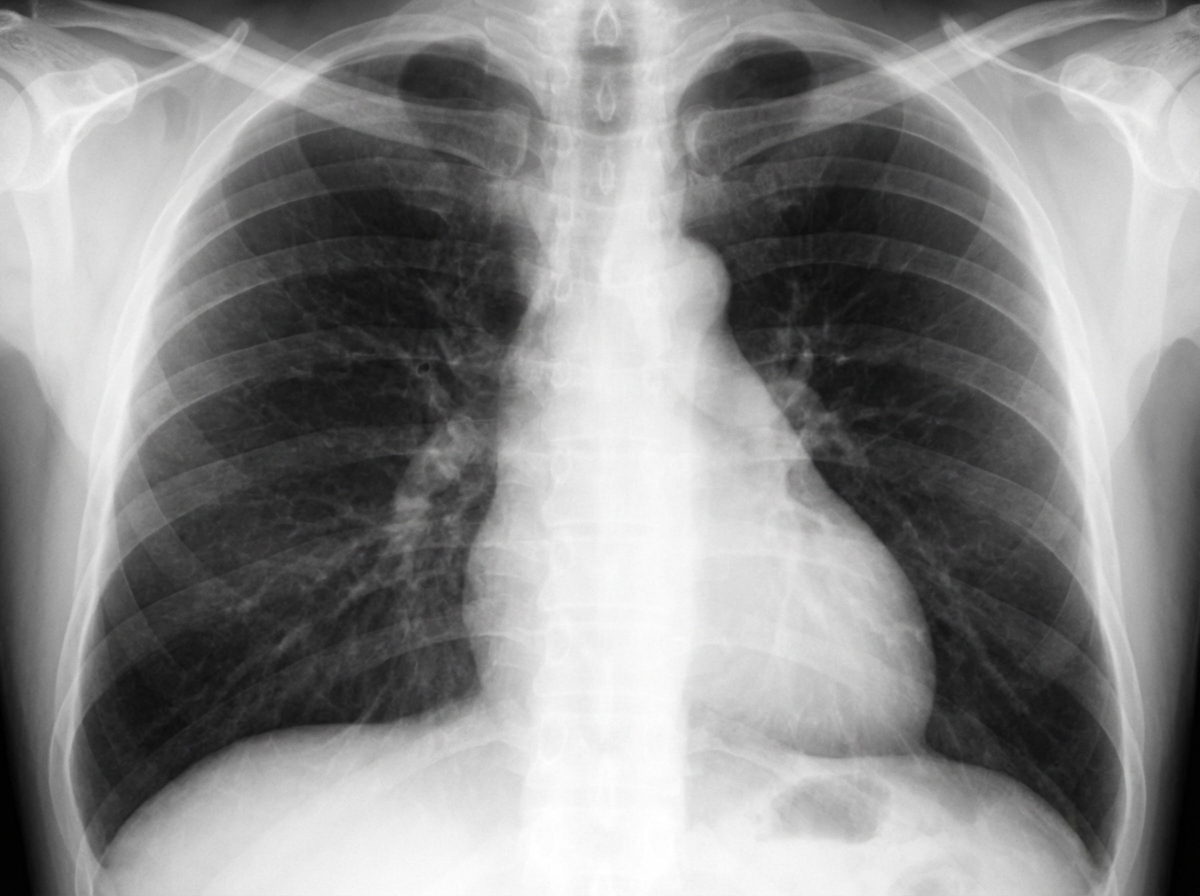

A 41-year-old male schoolteacher, a nonsmoker, presents with lightheadedness, shortness of breath, "lack of stamina," and chest pain. On physical examination, vital signs are normal. The patient is overweight with a BMI of 33. Cardiovascular examination reveals a left parasternal heave, a harsh grade 3/6 systolic flow murmur, and a loud P2 sound. Chest radiographs are shown. What is the most likely diagnosis?

Explanation: ***Pulmonary hypertension*** - The triad of **left parasternal heave** (indicating RV hypertrophy), **loud P2** (elevated pulmonary artery pressure), and **systolic flow murmur** strongly suggests **pulmonary arterial hypertension**. - Chest X-ray findings of **prominent pulmonary arteries**, **RV enlargement**, and **peripheral pruning** are classic for pulmonary hypertension in a nonsmoker. *Mitral stenosis* - Would present with **mid-diastolic rumbling murmur** at the apex, not a systolic flow murmur at the left sternal border. - Typically causes **left atrial enlargement** and **pulmonary edema** on chest X-ray, not RV hypertrophy signs. *Chronic bronchitis with cor pulmonale* - Usually occurs in **chronic smokers** with long-standing **COPD** and chronic hypoxemia, which doesn't fit this nonsmoker patient. - Would present with **productive cough**, **barrel chest**, and evidence of **chronic lung disease** on chest X-ray. *Deconditioning due to obesity* - Would not cause **loud P2**, **left parasternal heave**, or **systolic flow murmur** - these are specific cardiac findings. - Deconditioning typically presents with **fatigue** and **shortness of breath** on exertion without specific cardiac examination abnormalities.